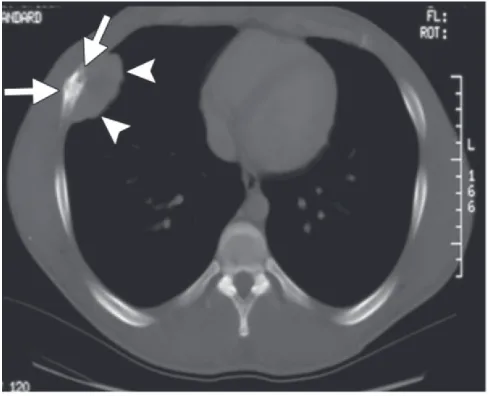

隣市の整形外科クリニックから, 肋骨腫瘍の若年成人の方が紹介されて来院されました.

持参されたCTでは, 骨が虫喰い状に破壊されており, ユーイング肉腫(Ewing sarcoma)など悪性骨腫瘍が疑われる所見. 造影MRIを急遽オーダーしました.

肋骨の内側と外側に腫瘤の形成が認められます.

引用元:Salimbene O. Primary chest wall Ewing sarcoma: Treatment and long-term results. Life 2024. 14.

最後に肋骨腫瘍の若年患者さんの造影MRIを確認. 骨内から骨外へ進展する腫瘍を認め, ユーイング肉腫を強く疑いました. 大学病院整形外科での診察を手配しました.

骨が壊れていて, その周りに腫瘤(骨外腫瘍)が形成されています.